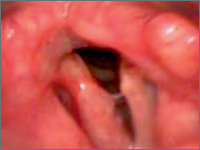

Gruźlica krtani u 64-letniego pacjenta

Laryngeal tuberculosis in 64-year old patient

GynecologyTuberculosis is a relatively common disease. Its incidence has decreased in recent years due to the the introduction of anti-tuberculosis therapy, increased standards of living and awareness among the population. Primary tuberculosis of the larynx is very rare, more often appearing as a secondary disease in the course of tuberculosis of the lungs. Primary TB accounts for less than 1% of all extrapulmonary forms of the disease. The main symptoms are hoarseness, a dry, irritating cough and a weakened voice.